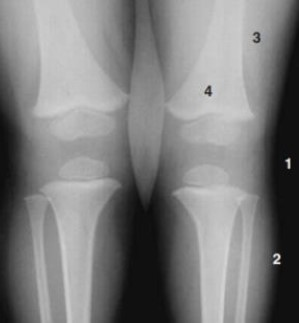

Quais das numerações presentes na figura, refere-se ao ar e à gordura, respectivamente?

Analise a figura.